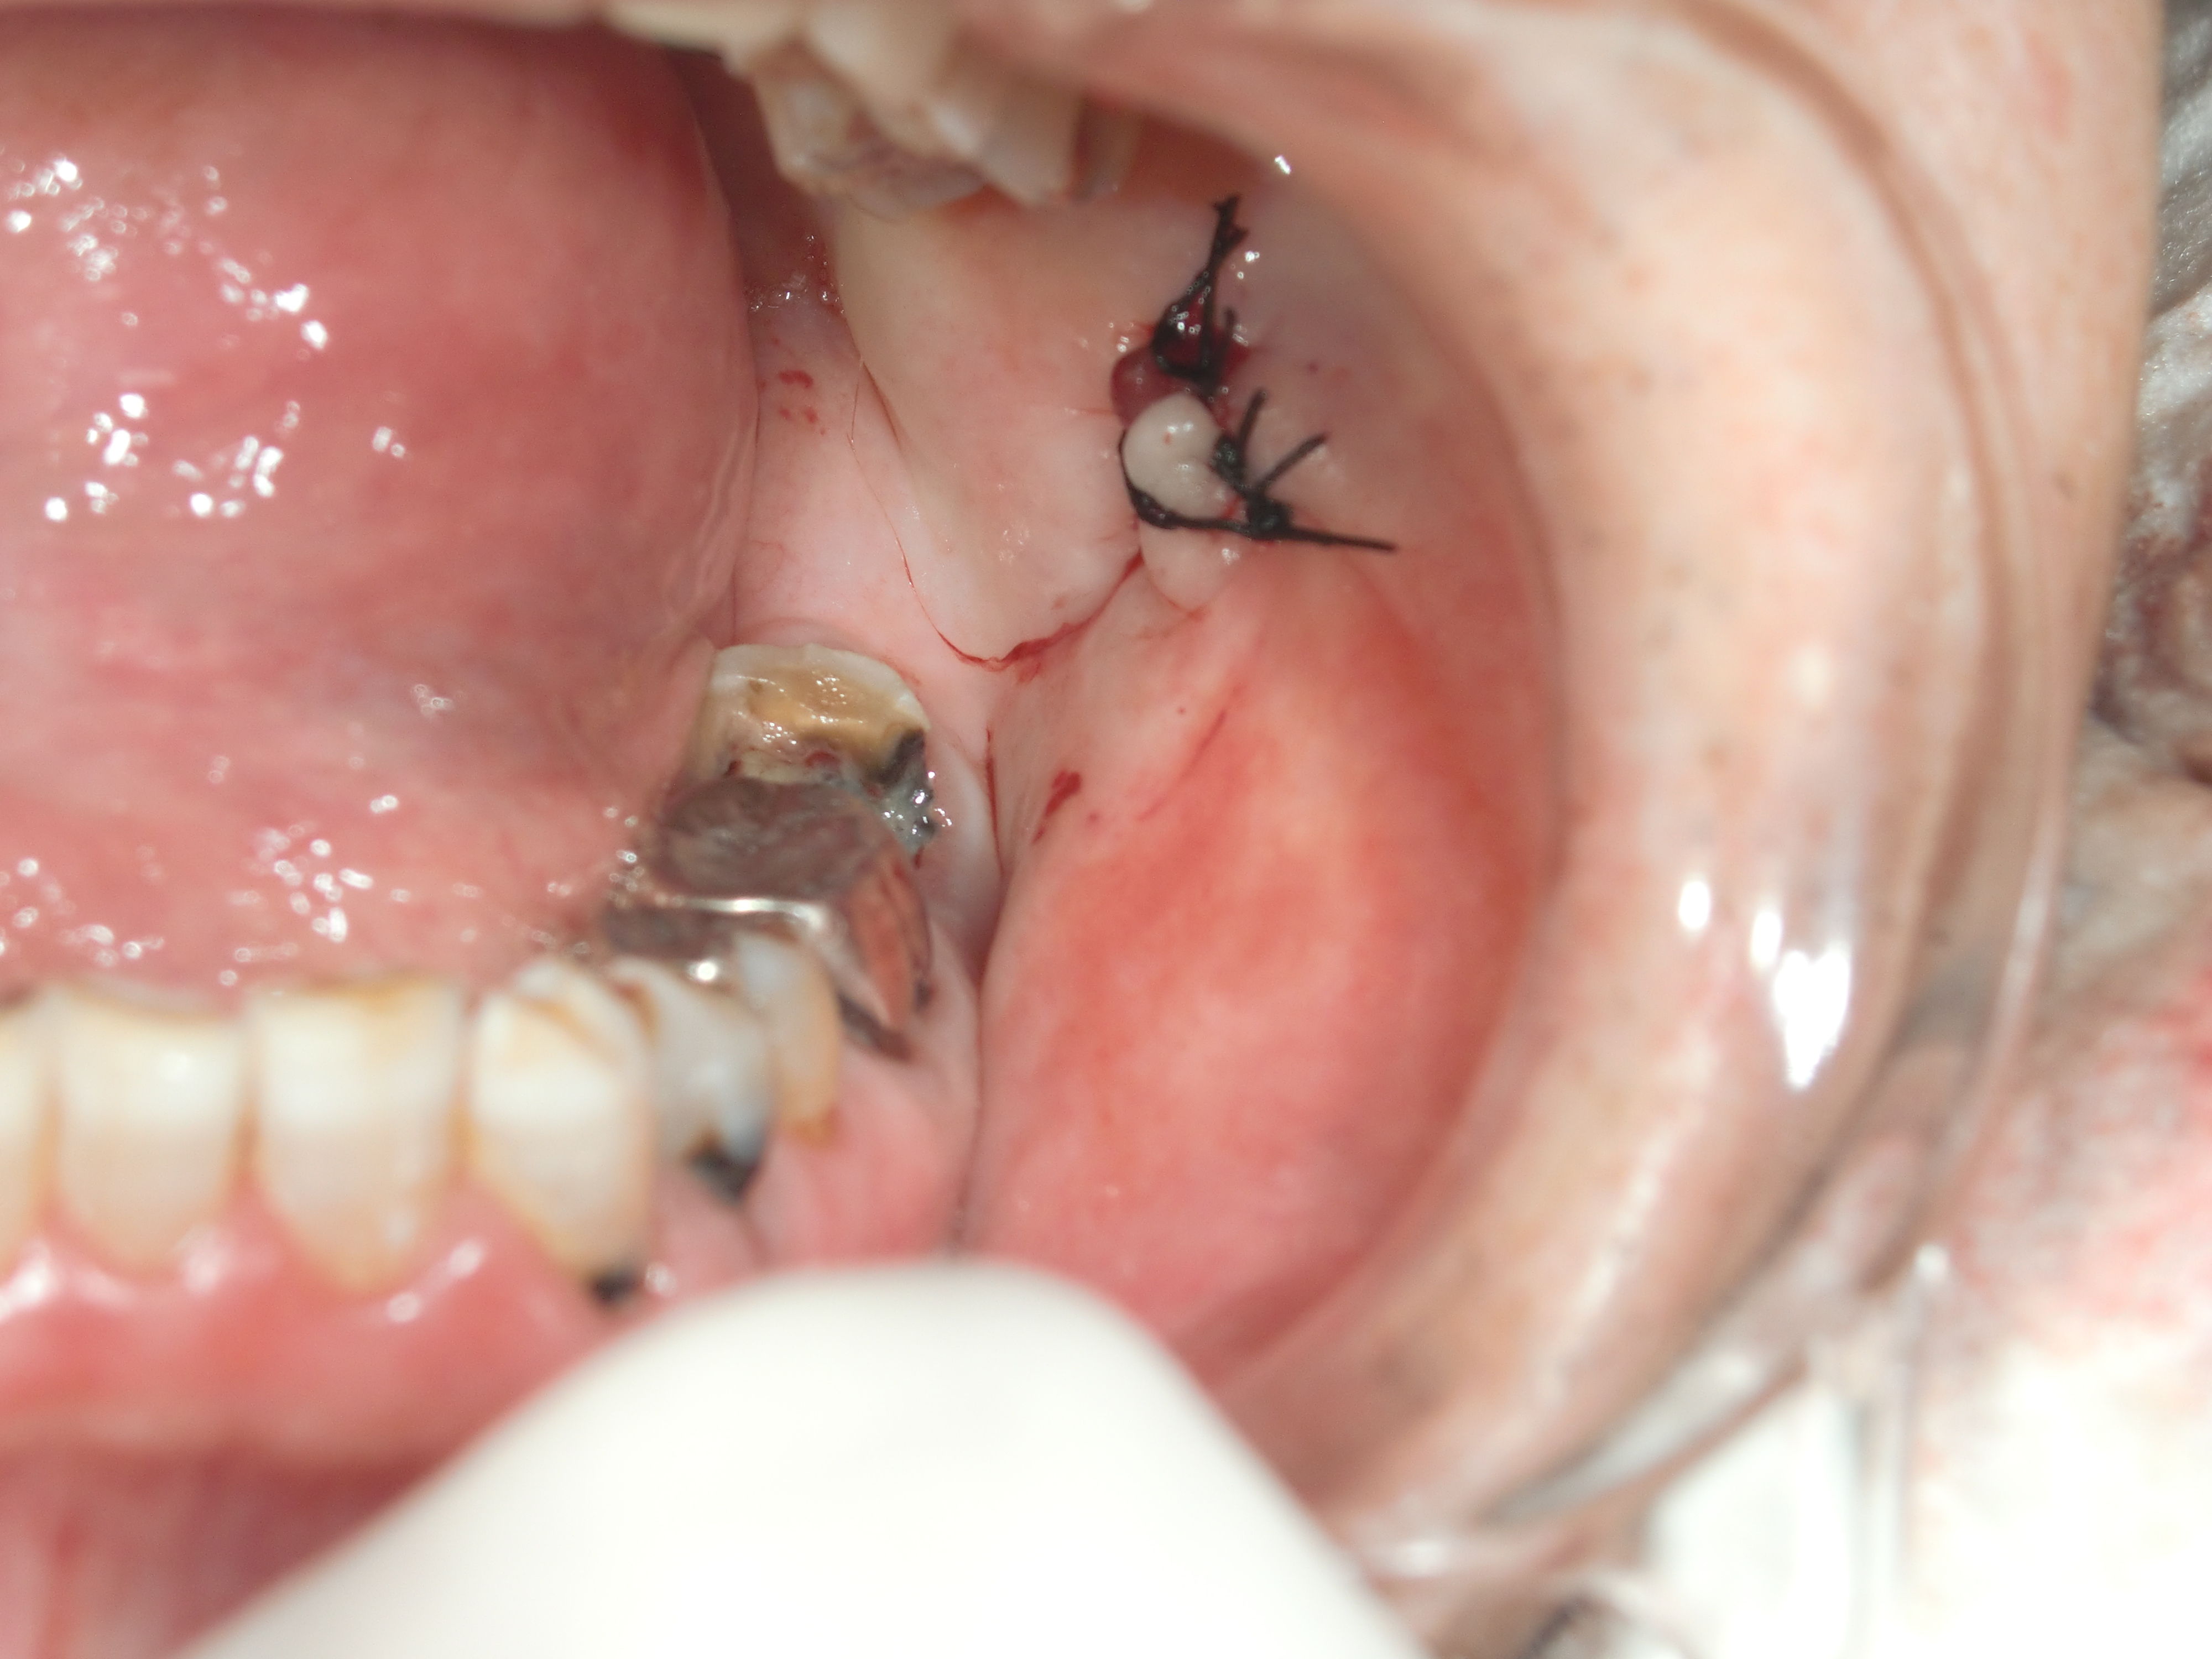

口腔内を確認すると、歯がかけていて、その部分が鋭利になっており、

それが頬を傷つけていたということがわかりました。

傷の部分を縫合し、歯の鋭利になっている部分を丸めるようにすれば

次の日には出血が全くなくなったと連絡がありました。